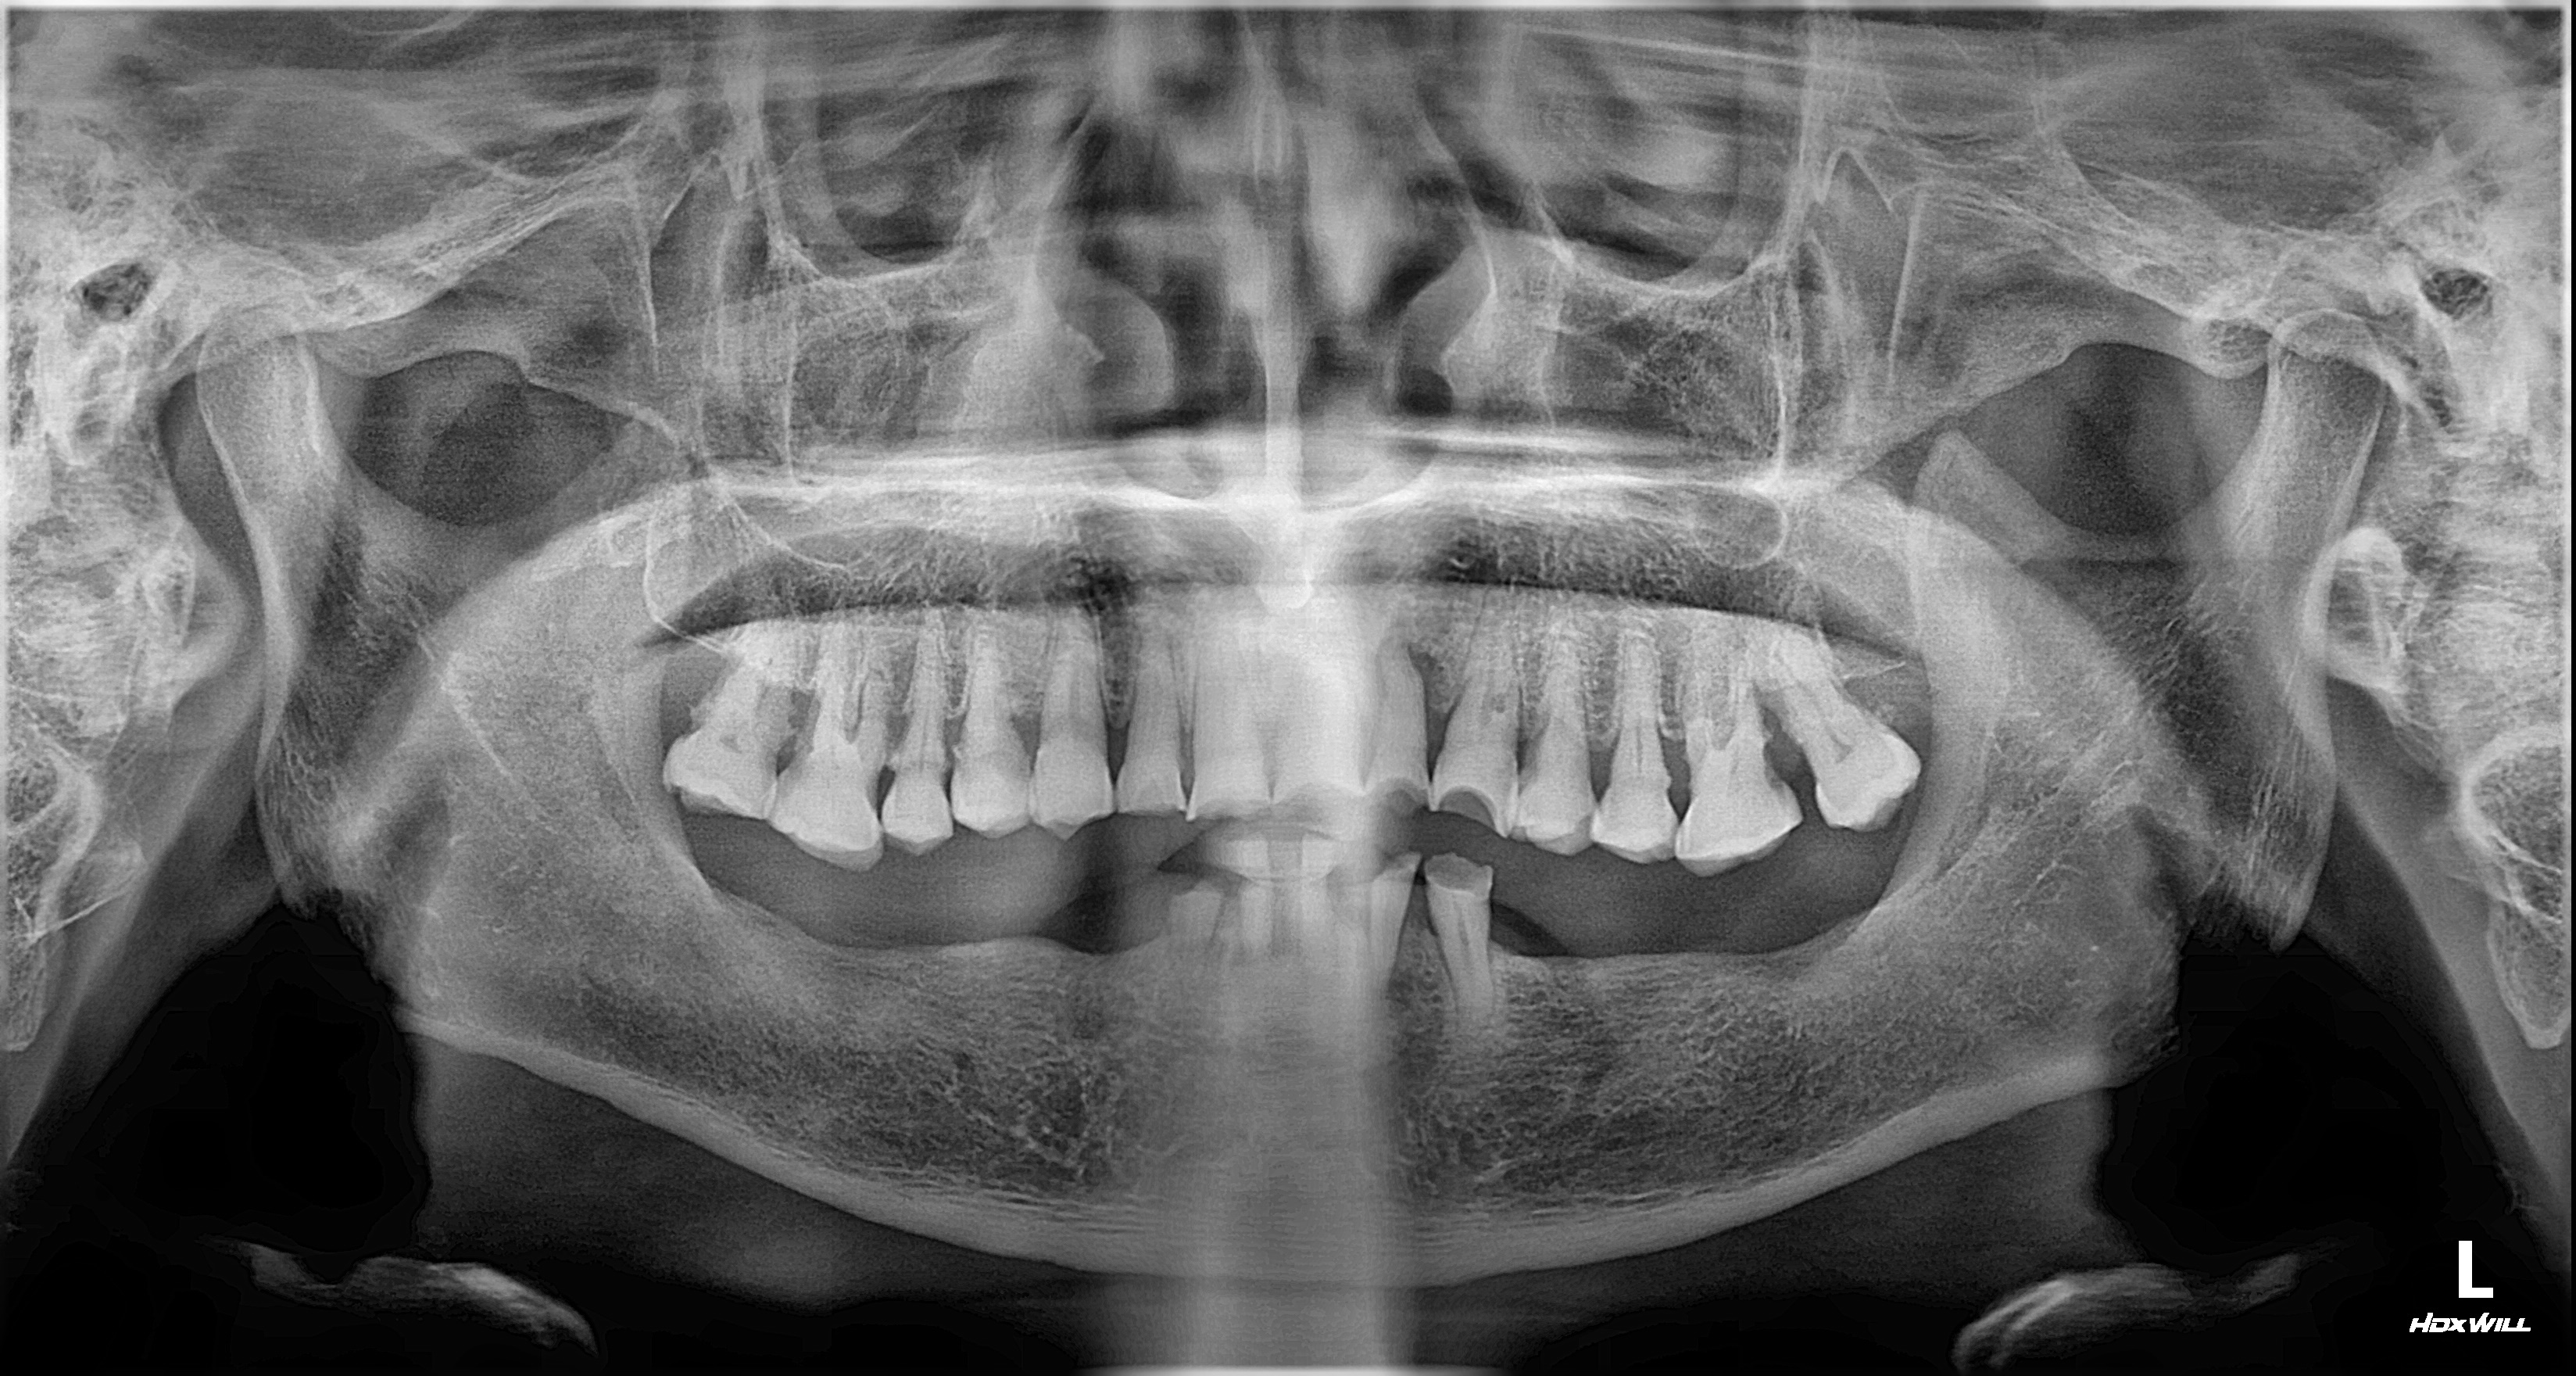

촬영일시: 2024.10.05.

촬영일시: 2025.03.29. [ 치료기간: 2024년 10월 05일 ~2025년 03월 29일 ] ※ 365서울앞선치과의원의 모든 컬럼은 각 진료과 의료진이 직접 작성합니다. 365서울앞선치과의원 임상 케이스 게시물은 환자분께 의학적으로 정확하고 상세한 정보를 드리기 위해 각 진료과 의료진이 직접 작성하며, 모든 증례 사진은 본원 의료진이 직접 시술한 증례를 촬영한 것으로, 의료법 제23조, 제56조에 의거하며 환자분의 동의를 얻어 포스팅에 사용하였습니다. 또한 해당 케이스는 본 환자분의 치료 결과이며, 환자 상태에 따라 치료의 결과는 달라질 수 있습니다. |